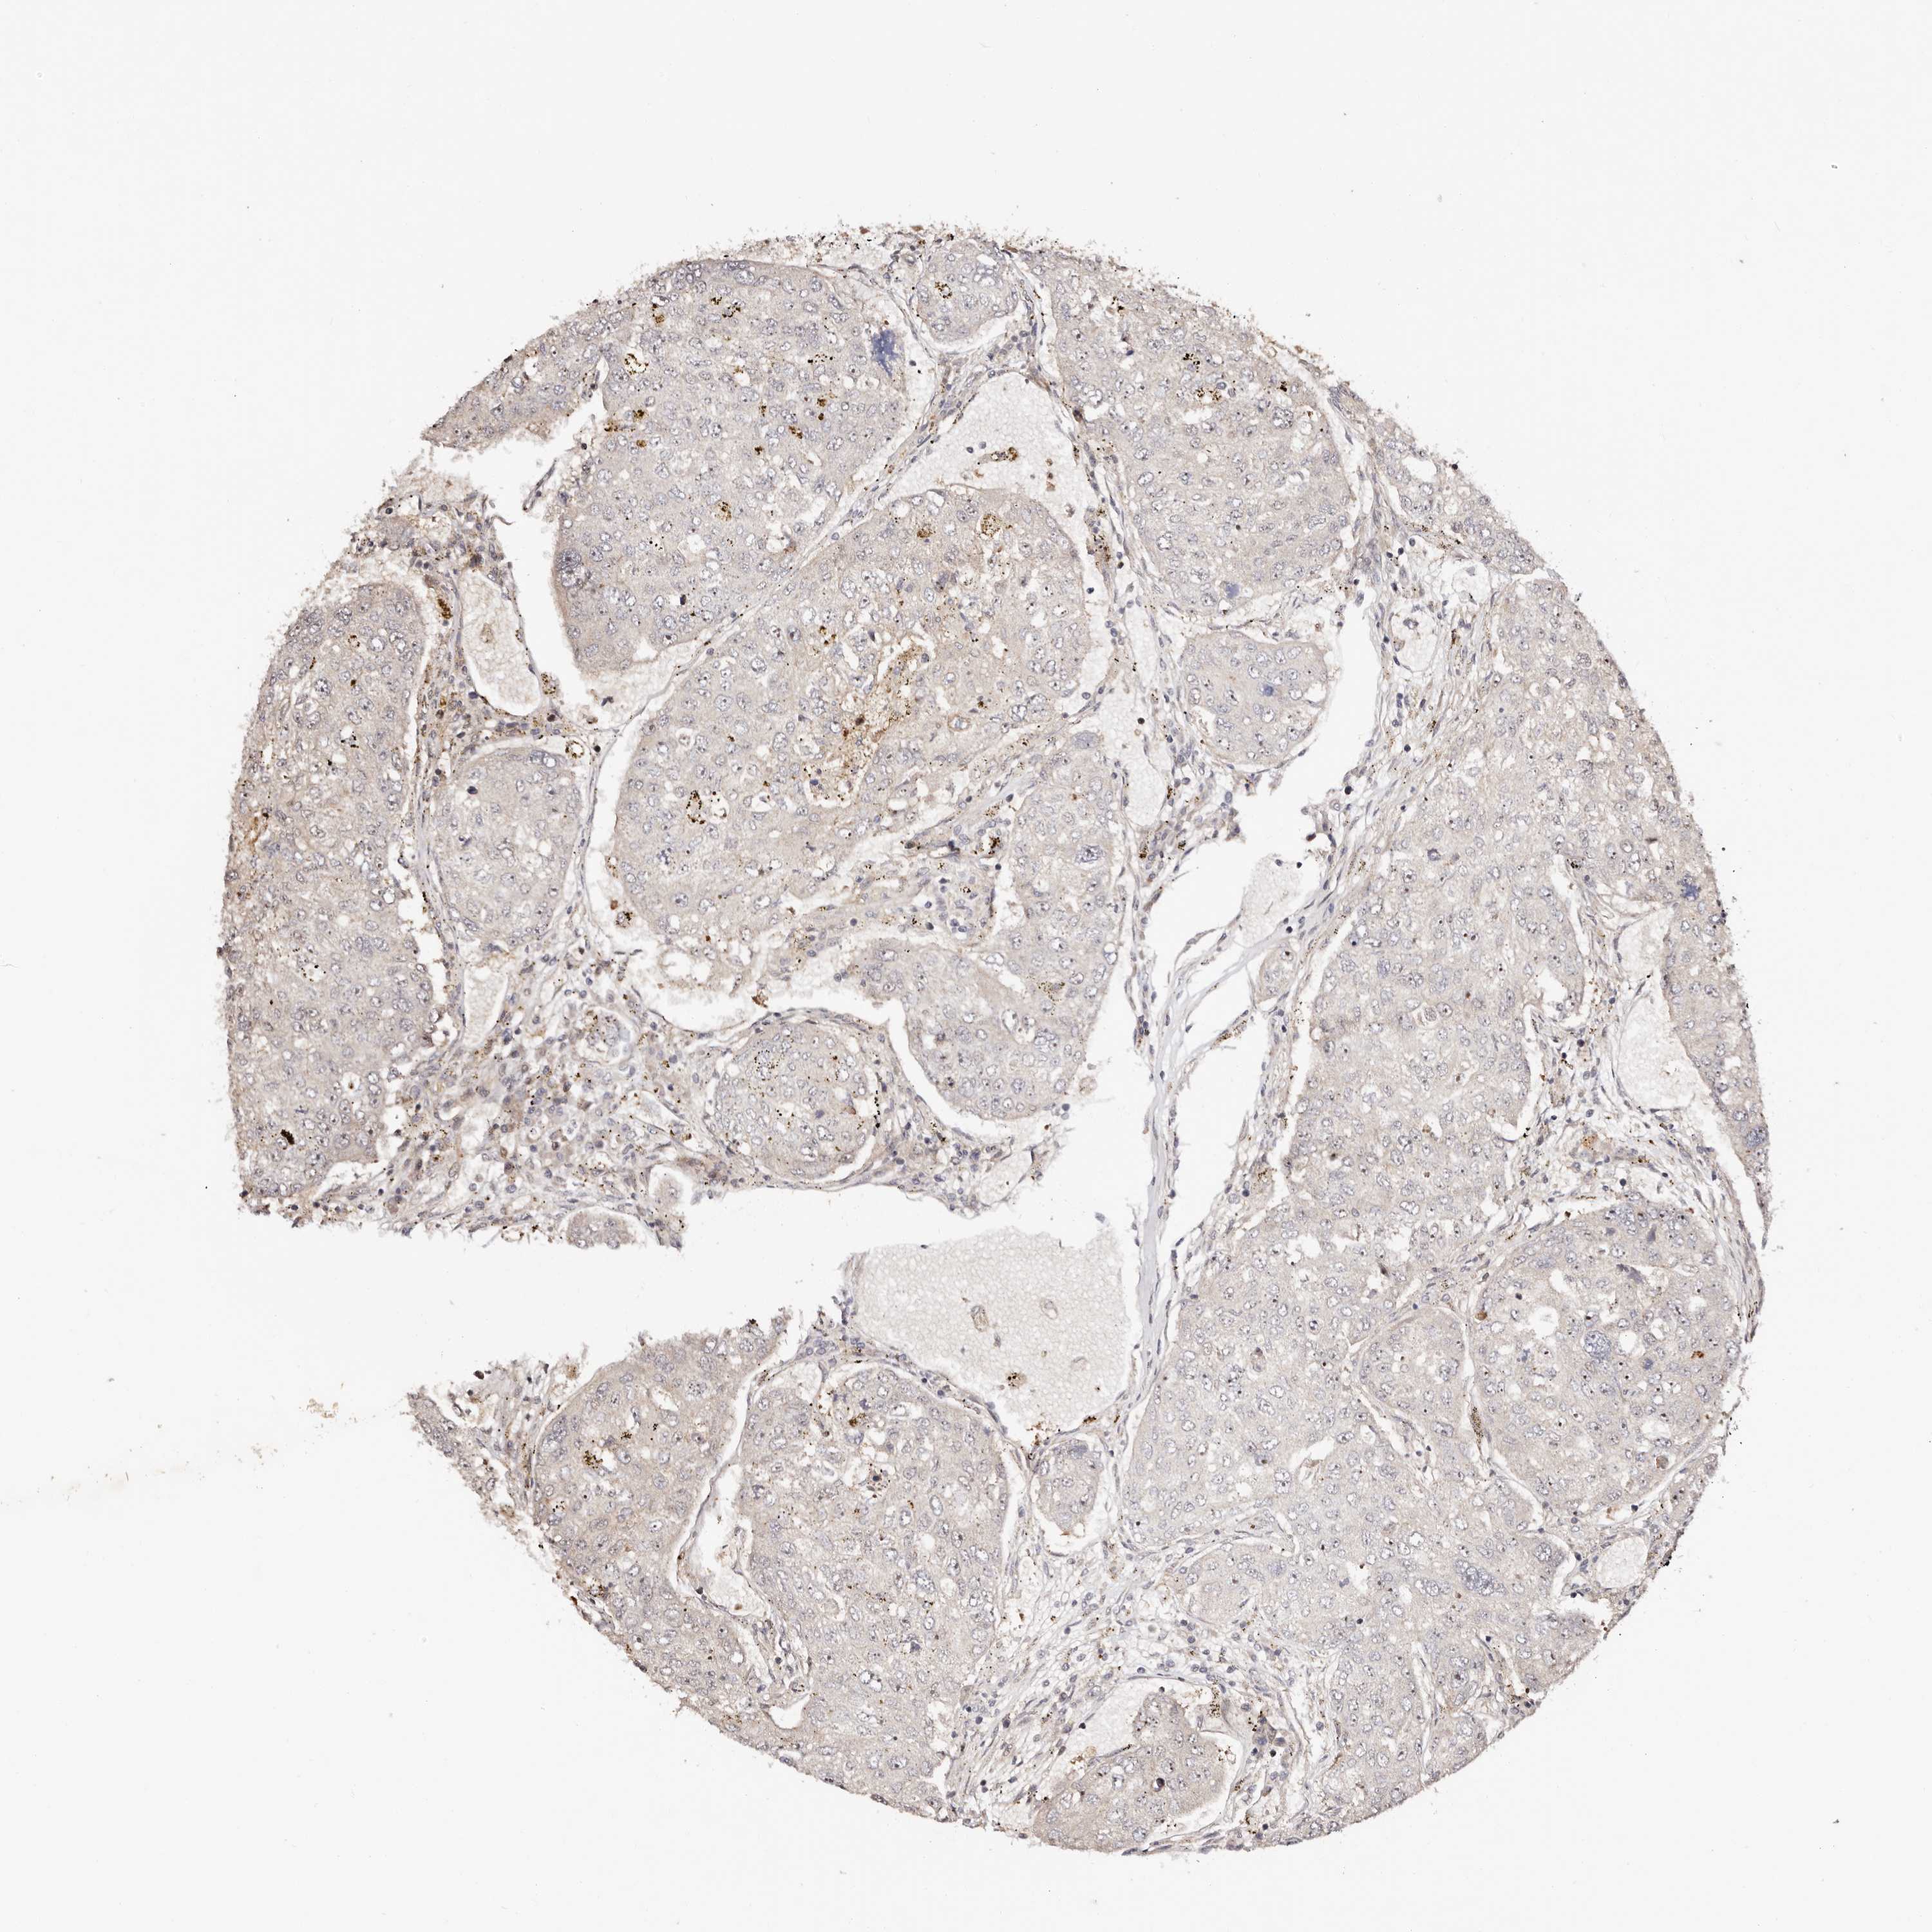

UROTHELIAL CANCER - Protein expressioni

A mouse-over function shows sample information and annotation data. Click on an image to view it in a full screen mode. Samples can be filtered based on level of antibody staining by selecting one or several of the following categories: high, medium, low and not detected. The assay and annotation is described here.

Note that samples used for immunohistochemistry by the Human Protein Atlas do not correspond to samples in the TCGA dataset.

Antibody stainingi

Antibody staining in the annotated cell types in the current human tissue is reported as not detected, low, medium, or high, based on conventional immunohistochemistry profiling in selected tissues. This score is based on the combination of the staining intensity and fraction of stained cells.

Each image is clickable and will lead to virtual microscopy that enables deeper exploration of all samples and also displays staining intensity scores, fraction scores and subcellular localization as well as patient and tissue information for each sample.

Antibody HPA028020

Antibody HPA028095

Antibody HPA028333

Urothelial carcinoma, Low grade

Urothelial carcinoma, High grade